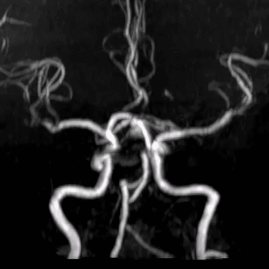

术前影像

CT及MRA:前交通动脉瘤。

造影显示:右侧Acom宽颈动脉瘤,大小约为7.5mm×10.5mm,动脉瘤底有双侧凸起,动脉瘤瘤颈宽,双侧A2段自动脉瘤侧壁发出。右侧A2起始直径1.7mm,左侧A2段起始部直径1.4mm。BOT试验显示左侧A1段不显影。